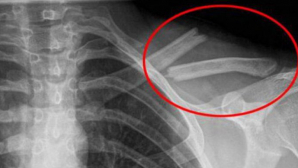

Taguri: suc acidulat O bei în fiecare zi! OTRAVA care îţi distruge oasele, iar tu nici nu bănuiai 1 ABCDEFGHIJKLMNOPQRSTUVWXYZ IMPORTANTE ALTELE